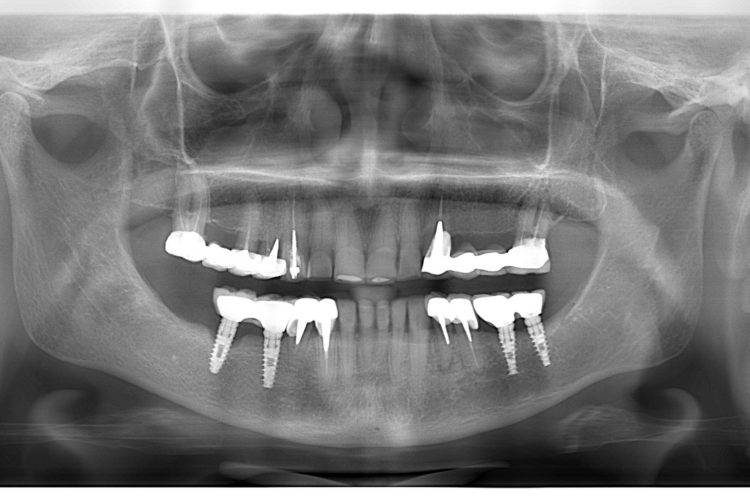

Pacienta in varsta de 74 ani s-a prezentat in clinica pentru reabilitare orala complexa si estetica. Planul de tratament a inclus implanturi Dentium, lucrari insurubate pe implanturi, fatete si coroane din hibrid